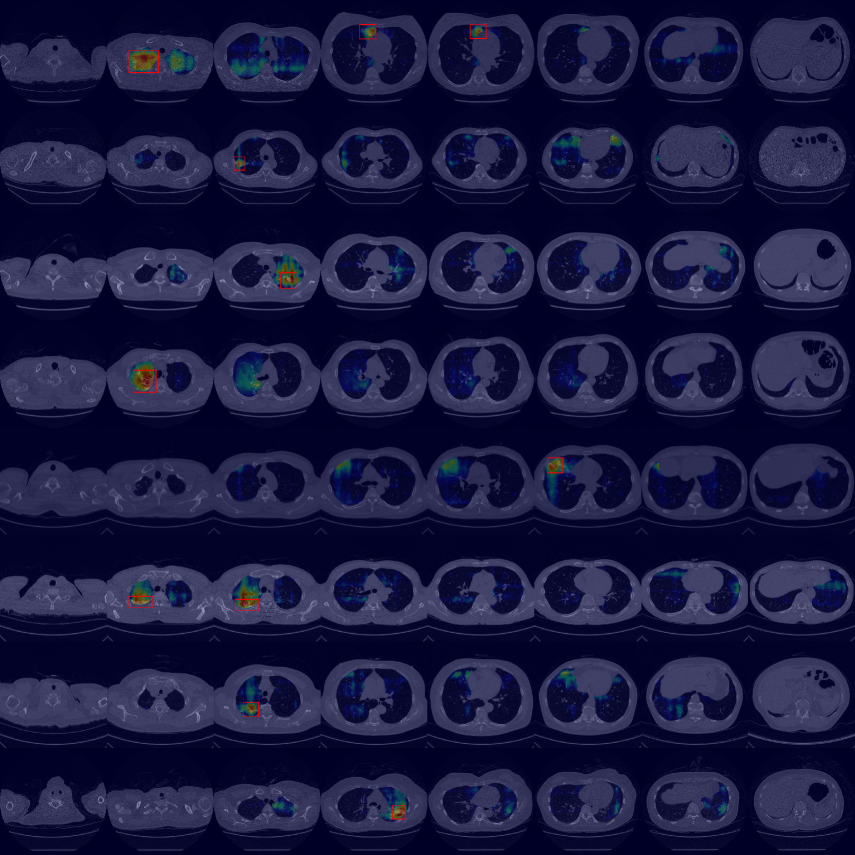

By using the internal clinical dataset from SMC of pneumonia and tuberculosis cases, we experimentally verified the superiority of the proposed VMPR-UAD through various comparative experiments. We also provide quantitative results and 3D abnormal (lesion) localization/visualization results of VMPR-UAD using the internal dataset for pneumonia and tuberculosis in the Supplementary Material to illustrate the superiority of anomaly localization by VMPR-UAD.

Finally, we evaluated the 3D abnormal (lesion) localization performance of the proposed VMPR-UAD. Of the 63 cancer cases in the MSD dataset with ground-truth annotations available, we excluded two cases (cases 38 and 96) of incorrect annotation or showing other diseases. We calculated whether the cancer area predicted by VMPR-UAD (binarized at a certain high-probability threshold) overlapped with the annotated cancer area. As a result, 57 of the 61 cases showed overlapping, demonstrating that VMPR-UAD can localize 3D lung anomalies (cancer in this case) with an accuracy of 93. Some localization examples in 3D data are shown in Fig. L. The red points in Fig. L(b) show the 3D cancer locations that the proposed method estimates with the highest confidence (i.e., location of highest pixel value in the 3D anomaly map). The red points in Fig. L(a) show the ground-truth cancer location. The ground truth and prediction shown in Fig. L confirm that VMPR-UAD correctly finds the lung anomaly 3D region. More detailed visualization results are available in the Supplementary Material. The prediction consistency can also be observed in 2D slices, as shown in Fig. M, where our anomaly localization map indicates correct cancer regions. Hence, the proposed VMPR-UAD can automatically localize or segment lesions without requiring any lesion information (i.e., using only CT slices from healthy subjects) for training.